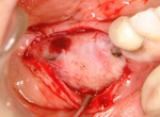

根面被覆(ルートカバレッジ) | ||

| 歯ぐきが薄い所は歯ぐきが下がりやすです。詰め物をしても詰め物の刺激でまた歯ぐきが下がってしまいます。再生療法により、露出根面をカバーし厚い歯ぐきを獲得しました。審美的にも改善され、歯ぐきも下がりにくくなりました。現在の歯科医療は進んでいます。 | ![]() |